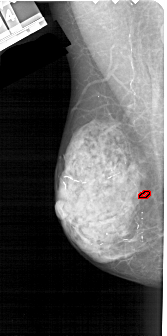

A_1223_1.LEFT_MLO

FILE: A_1223_1.LEFT_MLO.OVERLAY

TOTAL_ABNORMALITIES 1

ABNORMALITY 1

LESION_TYPE CALCIFICATION TYPE PLEOMORPHIC DISTRIBUTION CLUSTERED

ASSESSMENT 4

SUBTLETY 4

PATHOLOGY MALIGNANT

TOTAL_OUTLINES 1

BOUNDARY